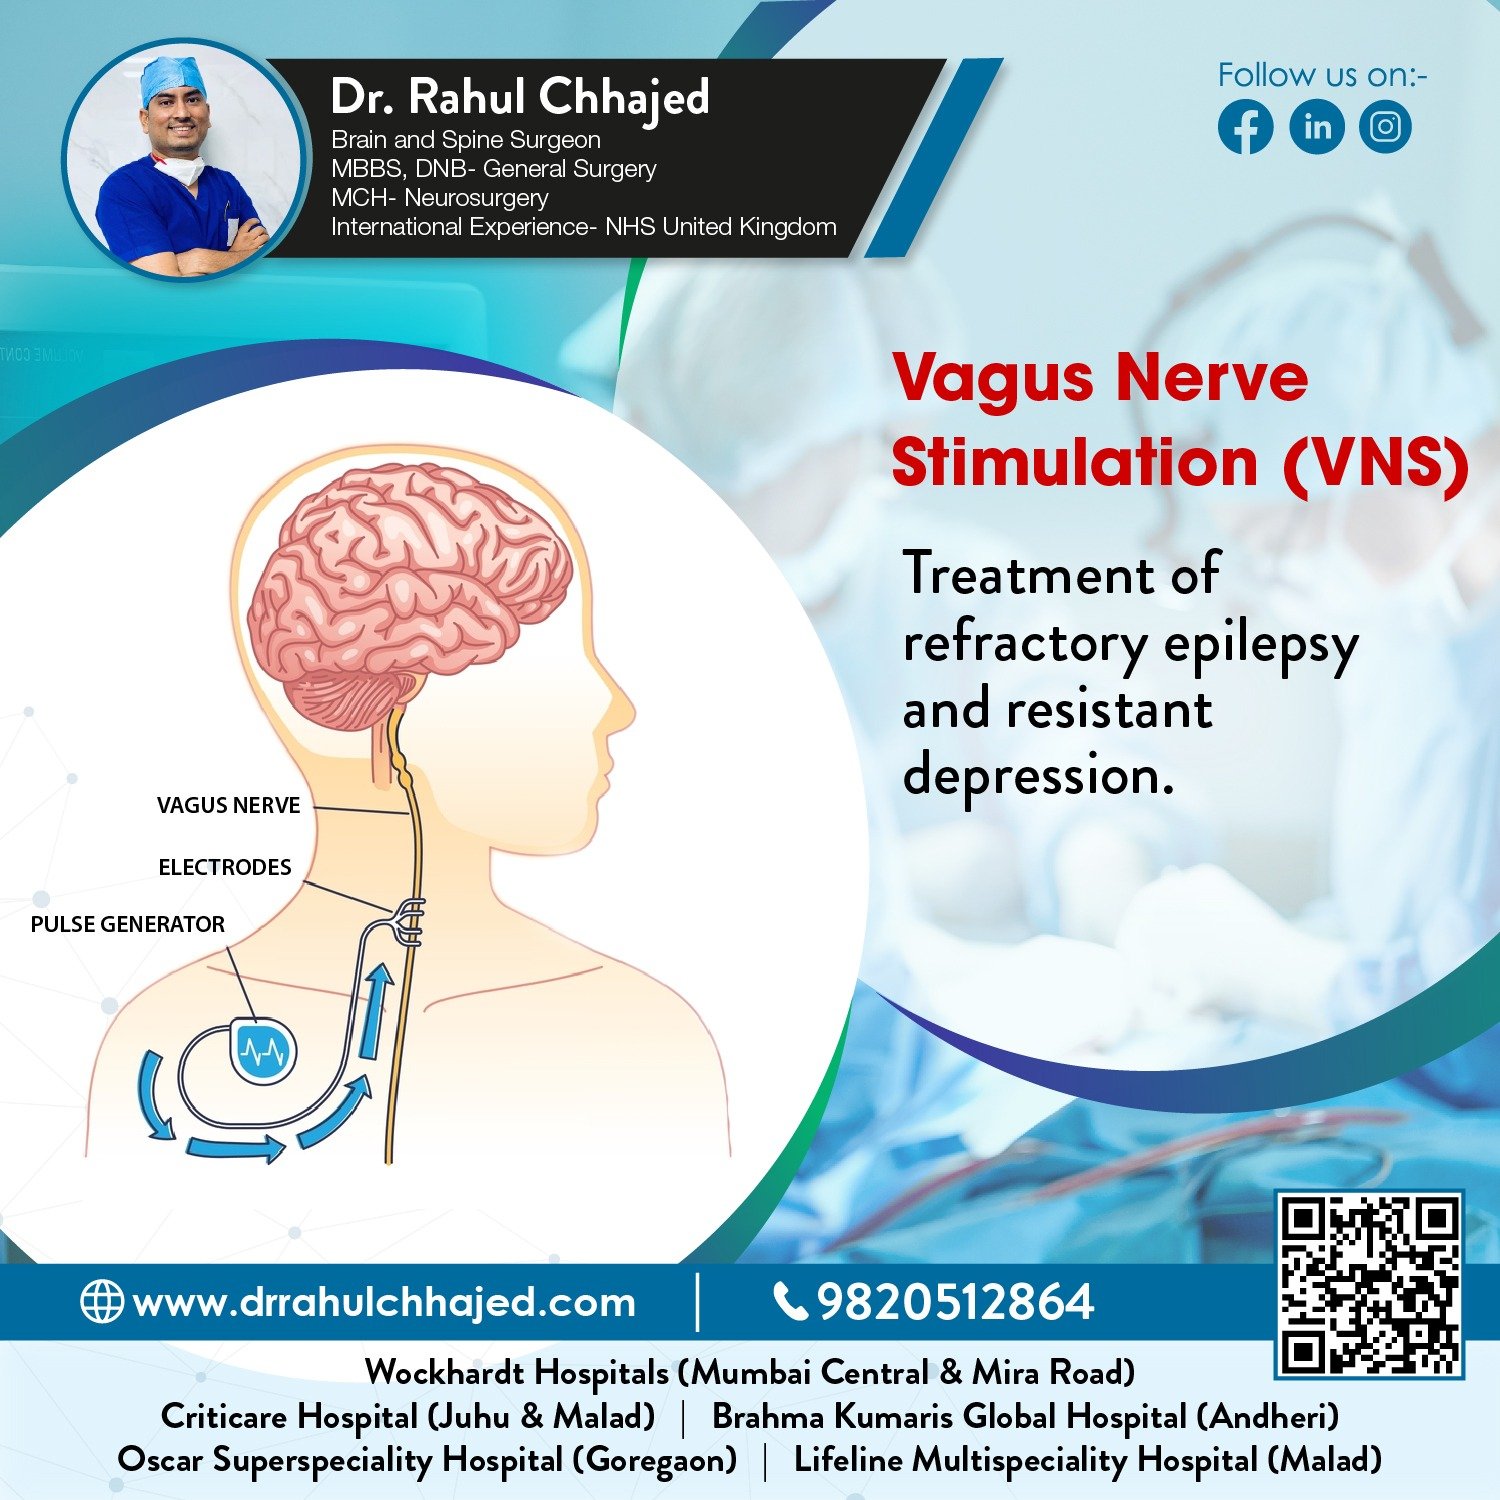

Epilepsy Surgery

Led by Dr.Rahul our practice offers advanced surgical options for medication-resistant epilepsy. Treatment includes resective surgery, laser therapy, and responsive neurostimulation. We provide personalized care to improve seizure control and quality of life for our patients.

Functional Neurosurgery focuses on surgically treating neurological conditions affecting brain function. Led by Dr.Rahul, our practice offers advanced interventions such as Deep Brain Stimulation and Intrathecal Drug Delivery Systems to improve quality of life for patients with movement disorders and chronic pain.